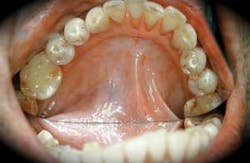

• In the early stage of submucous fibrosis, pigmented areas may be present and the tissue may even appear similar to lichen planus with a weblike appearance. This is termed a betel-quid lichenoid reaction that is usually found in younger individuals and is a response to tobacco products in the quid. In the early stage, petechia and increased melanin production may be noted. See Figure 3. Submucous fibrosis may also be preceded by vesicles in the early stages.